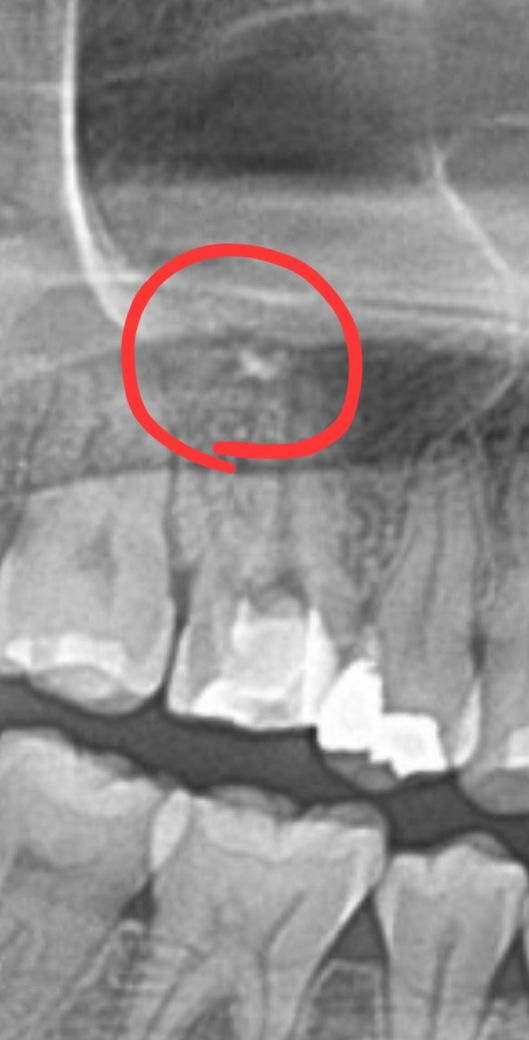

신경치료 중인데 하얀색 점이 발견되었습니다.

오늘 파노라마 사진 찍었는데,.저렇게 하얀색 점이 발견되었습니다.

혹시 과충전 된 걸까요??!

소독 2회 진행했는데, 2회차때 저렇게 생긴 것 같습니다.

현재 사진상 보이기로는 충전이 마무리된 상태가 아니고요 저건 최종 충전 물질이 아닙니다. 염증 상태 개선을 위해 첩약한 수산화 칼슘 재료가 좀 남아있는것 같습니다. 점차 흡수됩니다 걱정마세요

아직은 신경치료가 마무리가 안된거 같습니다. 약재가 살짝 넘어간경우는 발생할수 잇으며 크게 문제가 되진 않습니다.

사진으로 봤을 경우에는 충전이 되고 있는 상태가 아닌 것으로 보입니다. 신경치료를 할 때 재료가 치아 뿌리 끝을 넘어가는 과충전 증상이 있을 수 있지만 대부분 충전이 부족한 것보다는 예후가 좋은 경우가 많습니다.

자세한 확인을 위해서 치과에서 진료를 받아보는 것을 권유드립니다.